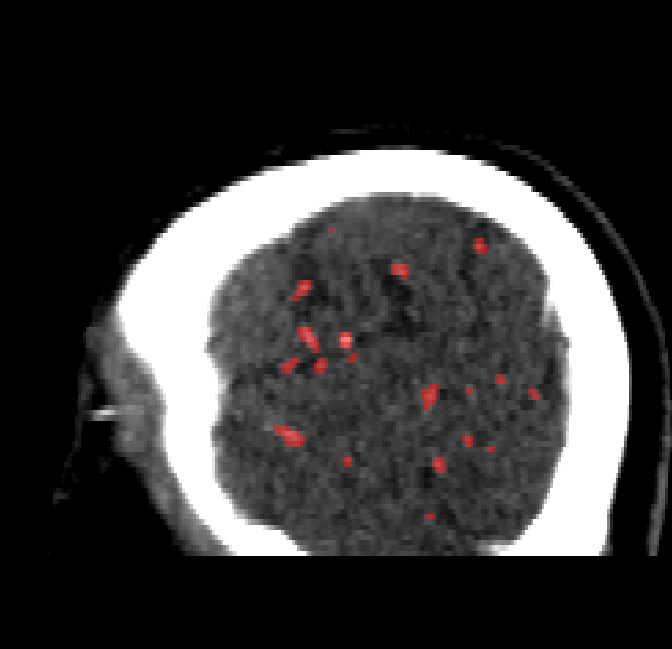

Refer to caption

Figure 4.9: Side view of segmentations. Unaltered image (left). No pretrain model (mid-left). Fine-tuned model (mid-right). Hand-labeled ground truth (right).

The models appear to have a hard time segmenting vessels close to the skull surface. The model trained exclusively on patient data appears to struggle far more for these types on conditions than the fine-tuned models. Figure 4.8 shows an example of the fine-tuneds model having close to no trouble segmenting vessels near the left side of the skull, while the baseline model suffers heavily from false negatives. To lesser degree, this effect can also be observed in the frontal lobe of Figure 4.9 In the other hand, Figure 4.7 presents an example of both models failing to segment vessels near the top of the skull.

In the other hand, it should be noted that fine-tuned models suffered from false positives more often than models with no pre-training. The fine-tuned models appeared to occasionally segment regions near the skull, which although similar in intensity to vessels, had no resemblance in terms of shape. Examples of this are seen in Figure 4.4 near the occipital bone and near the right temporal bone. Examples of oversegmentation were observed to happen commonly around the internal carotid arteries. This is likely due to the amount of contact surface between the artery and the surrounding bone. There was also a tendency for all model conditions to segment bone regions that were similar in shape to large vessels (Figures 4.3 and 4.4). Bone structures in such regions have similar pixel intensities to the arteries transporting contrast material, which could explain the source of confusion for a model.